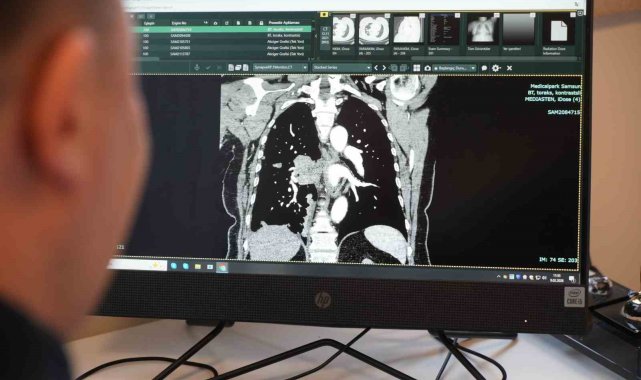

Göğüs Hastalıkları Uzmanı Prof. Dr. Şevket Özkaya, Türkiye'de sigara kullanımının özellikle kadınlar arasında alarm verici boyutlara ulaştığını söyledi. Özkaya, "Kadınlardaki sigara kullanımı artışı Cumhuriyet tarihinin rekor seviyesindedir" dedi.9 Şubat Sigarayı Bırakma Günü dolayısıyla değerlendirmelerde bulunan Prof. Dr. Özkaya, "2012 ile 2022 yılları arasındaki verilere baktığımızda, ülkemizde sigara içme oranı genel olarak yüzde 20 arttı. Erkeklerde bu artış yüzde 12 düzeyindeyken, kadınlarda yüzde 38 gibi çok ciddi bir artış söz konusudur. Bugün erkeklerin yüzde 45'i, kadınların ise yüzde 19'u sigara içiyor. Özellikle 35-44 yaş grubundaki kadınlarda tütün kullanımı Cumhuriyet tarihinin en yüksek seviyelerine ulaştı. Bu yaş grubunda her dört kadından biri sigara içiyor" dedi."Sigara kullanımının artması, gençlerde ve çocuklarda sigarayla temas riskini de artıracak"Kadınlarda sigara bağımlılığının artmasının toplumsal sonuçları olduğuna vurgu yapan Prof. Dr. Özkaya, "Kadın, anne figürü toplumda önemli bir rol modeldir. Kadınlarda sigara kullanımının artması, gençlerde ve çocuklarda sigarayla temas riskini de artıracaktır. İkinci önemli sorun ise kadınların sigarayı bırakmasının erkeklere göre daha zor olmasıdır. Bırakma oranları erkeklerin gerisinde seyrediyor" şeklinde konuştu."Kadınlarda akciğer kanseri vakaları belirgin şekilde artıyor"Akciğer kanseri vakalarındaki artışa da dikkat çeken Özkaya, "Son yıllarda hem sigara içen hem de hiç sigara kullanmamış bireylerde akciğer kanseri vakalarında dikkat çekici bir artış görüyoruz. Özellikle kadınlarda adenokarsinom tipi akciğer kanseri belirgin şekilde artış göstermektedir., Yapılan son araştırmalara göre akciğer kanseri teşhislerinin yaklaşık yüzde 20'si hiç sigara içmemiş bireylerde konuluyor. Bunun en önemli nedeni pasif içiciliktir. Yani siz sigara içmeseniz bile, yakın çevrenizde sigara içiliyorsa akciğer kanseri riskiyle karşı karşıya kalabilirsiniz" ifadelerini kullandı."Sigara kadınlarda kalp krizi ve cinsiyete özgü kanserleri de artırıyor"Sigaranın kadın sağlığı üzerindeki etkilerine değinen Prof. Dr. Özkaya, "Sigara kullanımı kadınlarda sadece akciğer kanseri riskini değil, kalp krizi riskini de ciddi şekilde artırmaktadır. Ayrıca gebelikle ilgili sorunlar, bebek sağlığı problemleri ve rahim ağzı kanseri gibi cinsiyete özgü hastalıklar da sigarayla doğrudan ilişkilidir" dedi.Özkaya sözlerini şöyle tamamladı:"Sigara içen kadınlarda, kanserle ilişkili bazı gen mutasyonlarını erkek içicilere göre daha sık görüyoruz. Bu nedenle kadınlarda sigara kullanımı, çok daha dikkatle ele alınması gereken önemli bir halk sağlığı sorunudur."